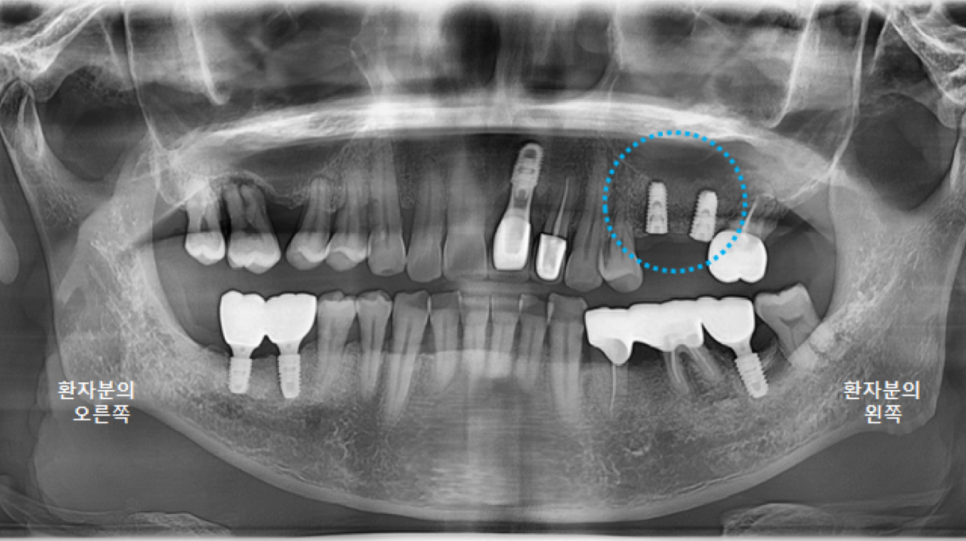

보철물을 다 붙이고 나서 촬영한 파노라마 엑스레이입니다.

앞니가 들어가서 심미적으로도 좋아졌고,

교합 평면도 좋아졌습니다.

이제 환자분의 식사가 조금 더 편해져서, 잘 드실 수 있게 되었습니다. ^^

그리고 다시 파노라마 엑스레이를 촬영했습니다.

최상의 컨디션은 아니지만,

어느정도 치유가 되었기에 3차원 CT 촬영 후, 왼쪽아래 큰어금니 임플란트 수술을 진행하도록 합니다.